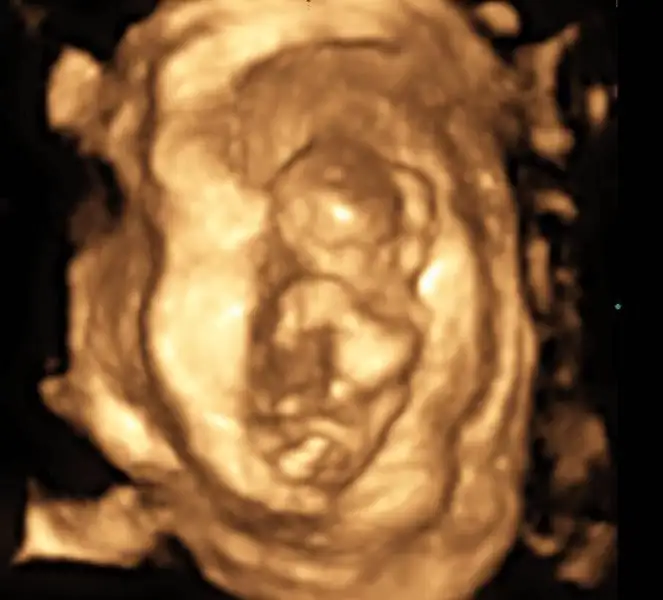

nub teorisi var canim resim at bakalim nasil

Eklentiler

• 1.webp

1.webp

25,3 KB · Görüntüleme: 76